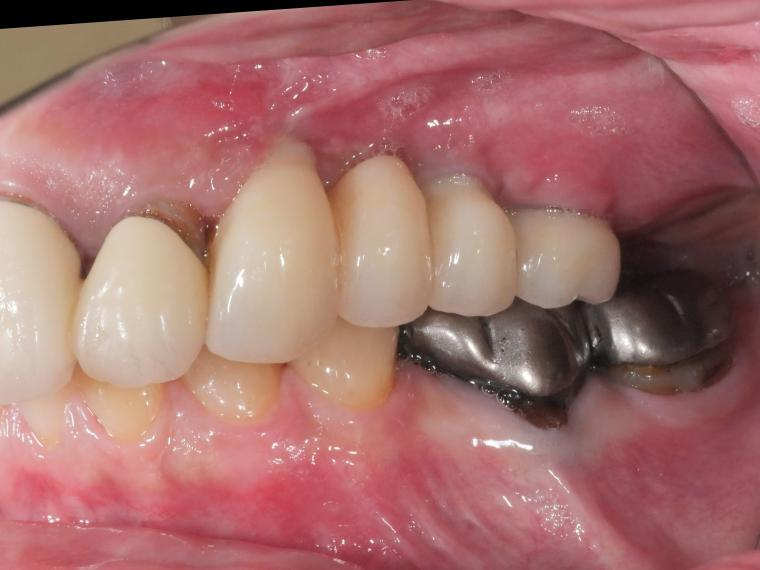

AFTER

ご来院時から欠損状態だった左上第一小臼歯から第一大臼歯も含め、欠損補綴についてお話させていただき、

インプラントでの治療を選択されました。